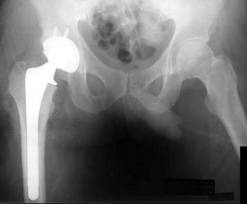

Many Musicians who perform live have had hip ailments. Rumor has it Prince needs double hip replacement surgery, but after conversion to Jehovah’s Witness he wishes to avoid the blood associated hip surgery. Another musician who struggled with hip pain Steve Perry, of Journey fame, ultimately had the hip replacement procedure. Perry was afflicted with hip problems at an earlier age, and it affected planned concert tours leading to his departure from the band. Many patients, especially those who have hip degeneration at younger ages wish to delay or prevent hip replacement surgery. Many have turned to Regenerative Medicine and Stem Cell Therapy.

Regenerative procedures such as stem cells, harness the healing potential of the bodies own repair system to deliver regenerative potential in degenerative arthritis. Avascular Necrosis (AVN) has also been treated with Stem Cell Therapy. The ability to delay hip replacement in younger patients, or prevent further degeneration is a desirable goal.

Degenerative arthritis may be a secondary problem with Avascular Necrosis (AVN), complicating the treatment. Patients with AVN desiring to avoid hip replacement, have opted for stem cell treatment for this reason. Degenerative arthritis is affected by many factors including prior trauma. Addressing precipitant factors with a regenerative approach may provide the best opportunity for successful results and be an alternative strategy to hip replacement surgery.